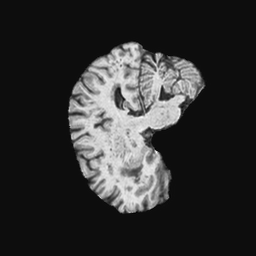

Exp. 2: Fetal brain data is used to test the robustness of our approach under real conditions. Fetuses younger than 30 weeks very often move a lot during examination. Fast MRI sequences allow artifact free acquisition of individual slices but motion between slices corrupts consistent 3D information. Fig. 3 shows that our method is able to accurately predict Ti^^subscript𝑇𝑖\hat{T_{i}} also under these conditions. For this experiment we use ωisubscript𝜔𝑖{\omega_{i}} from three orthogonally overlapping stacks of ssFSE slices covering the fetal brain with approximately 20-30 slices each. We are ignoring the stack transformations relative to the scanner and treat each ωisubscript𝜔𝑖{\omega_{i}} individually. For ΩtrainsubscriptΩ𝑡𝑟𝑎𝑖𝑛\Omega_{train}, 28 clinically approved motion compensated brain reconstructions are resampled into a 150×150×150150150150150\times 150\times 150 volume with 1mm×1mm×1mm1𝑚𝑚1𝑚𝑚1𝑚𝑚1mm\times 1mm\times 1mm spacing. A density of 500 unique sampling normals has been chosen via the Fibonacci sphere sampling method with 25 sampling planes evenly spaced between -25 to +25 on the Z-axis. This gives a plane spacing of 2mm, sampling only the middle portion of the fetal brain. Training took approximately 10hrs for 30 epochs. Prediction, i.e., the forward pass through the network, takes approx. 12 ms/slice.

Refer to caption

(a)

(b)

(c)

(d)

(e)

(f)

Figure 3: Comparison of a single slice from a heavily motion corrupted stack of ssFSE T2 weighted fetal brain MRI (a); axial multi planar reconstruction of one sagittal input stack (b); a slice at approximately the same position through a randomly selected training volume (c); failed reconstruction attempt using standard SVR based on three orthogonal stacks of 2D slices (d) (the fetus moved heavily between the acquisition of the individual stacks); reconstruction based on SVRNet Ti^^subscript𝑇𝑖\hat{T_{i}} regression (e); SVR initialised with SVRNet transformations after eight iterations of SVR (f). Note that (e) and (f) are reconstructed directly in canonical atlas co-ordinates.